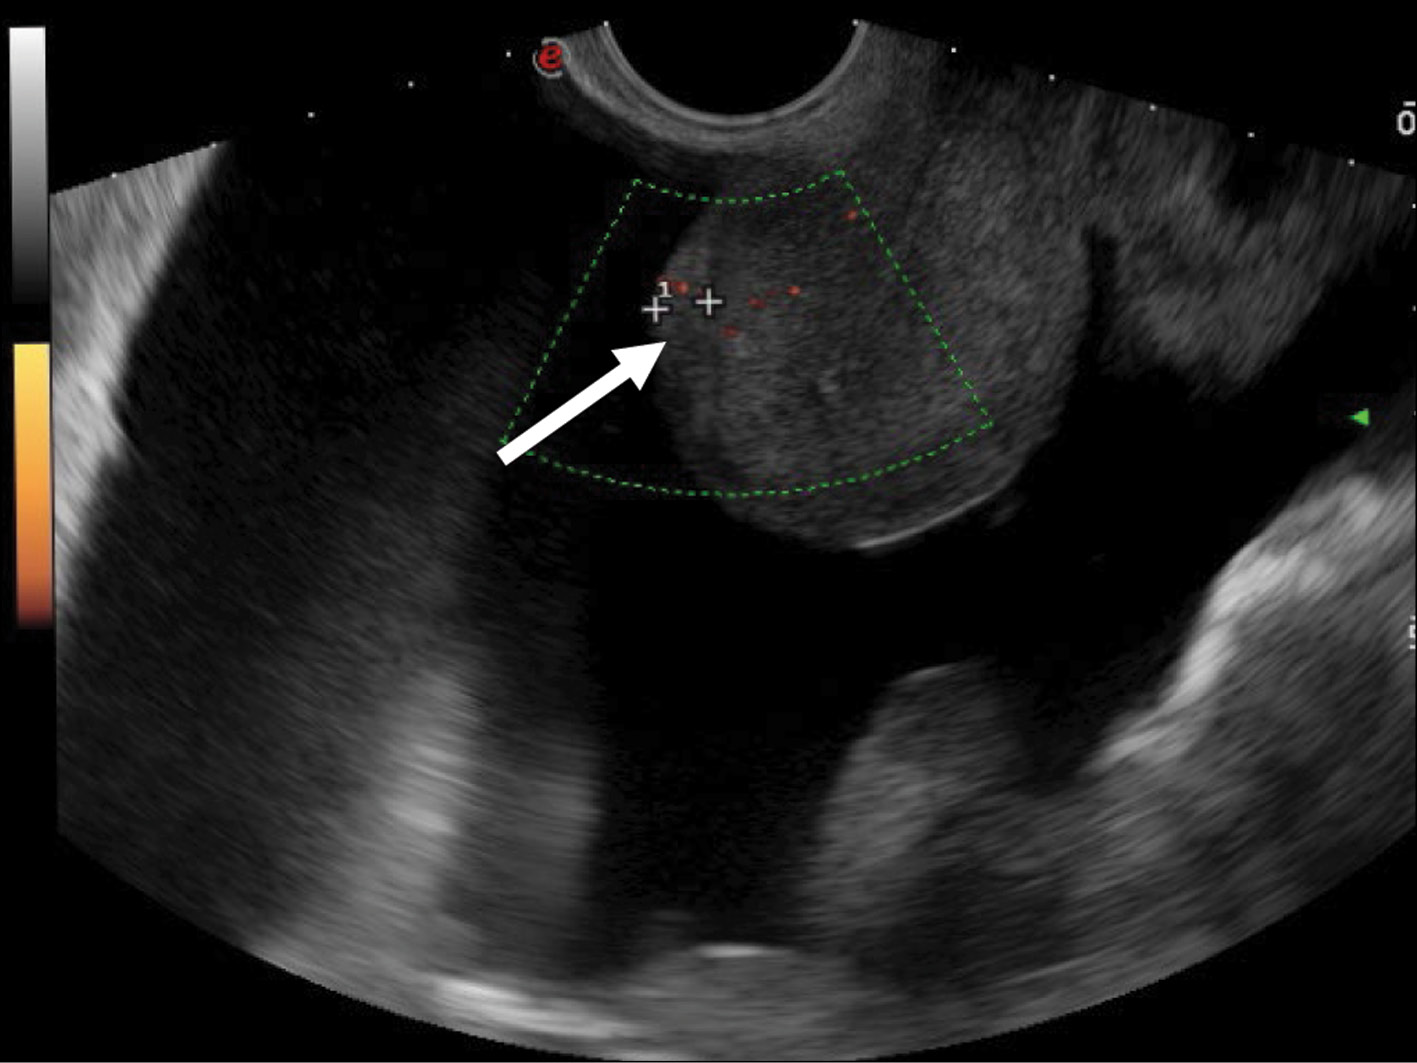

Figure 2 shows uneven thickening of the pelvic peritoneum covering the anterior wall of the uterus. The structure of the blastomatously altered peritoneum of the small pelvis is isohypoechoic, with ill-defined edges on the interface with the body of the uterus.

Fig. 2. Dopplerography in the energy mode. Malignant struma ovarii. Carcinomatosis of the pelvic peritoneum anterior to the uterus (arrow). The visualized tumor lesion is 6 mm thick.

The intensity of the blood flow in the tumor lesion in the retrouterine pouch is remarkable, as well as its smoothness in the thickened (up to 5–7 mm) peritoneum of the small pelvis (Fig. 3).